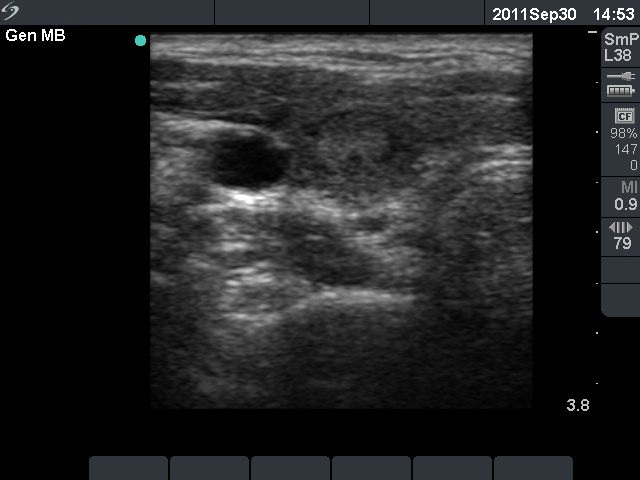

First examination (first row):

Clinical presentation: a 17-year-old girl who has been treated for hyperthyroidism for 2 years. She had no complaints.

Palpation: no abnormality.

Functional state: euthyroidism on daily 10 mg methimazole with TSH 2.14 mIU/L, FT4 13.2 pM/L.

Ultrasonography: the thyroid was echonormal with a hyperechogenic lesion in the central part of the right lobe. The vascularization was a little bit increased.Suggestion: discontinuation of thyrostatic therapy and follow-up examination 6 months later.